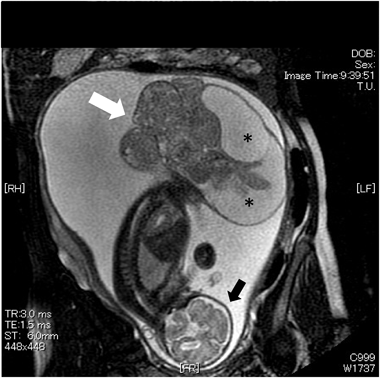

胎児心エコー所見をもとに早期娩出し救命できたハイリスク仙尾部奇形腫の胎児例Successful Preterm Delivery of a Fetus with High-risk Sacrococcygeal Teratoma Based on Fetal Echocardiographic Findings